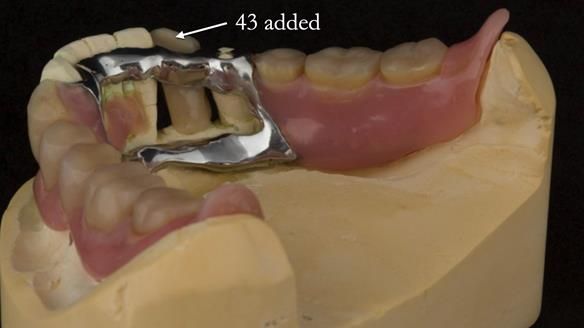

In 2022, tooth 43 fractured.

An artificial tooth was added to the RPD

by welding a cobalt–chrome tag to the bar

and adding the tooth.

The denture continued to function extremely well.